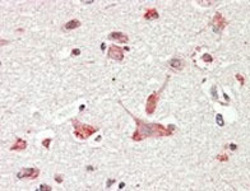

Supportive validation

- Submitted by

- Abnova Corporation (provider)

- Main image

- Experimental details

- GOLGA6A/GOLGA6B polyclonal antibody (Cat # PAB6865) (3.8 ug/mL) staining of paraffin embedded human cerebral cortex. Steamed antigen retrieval with citrate buffer pH 6, AP-staining.

- Validation comment

- Immunohistochemistry (Formalin/PFA-fixed paraffin-embedded sections)